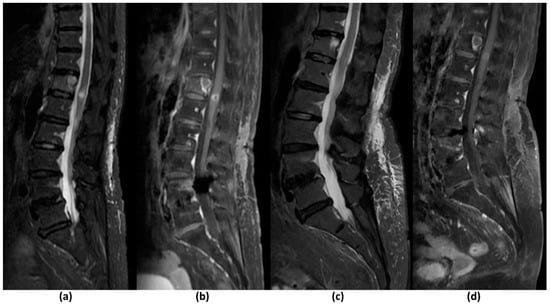

Pathological vertebral body fracture/collapse is known to result in MSCC [5,58] and it is important to distinguish benign osteoporotic compression fractures from malignant vertebral compression fractures (VCF) on imaging due to the significant implications on treatment (Figure 4). MR findings that have been shown to suggest a malignant aetiology include an expansile convex posterior cortex, marrow signal abnormalities of the posterior elements, destruction of the pedicles, heterogeneously increased enhancement of the vertebral body, abnormal epidural or paraspinal soft tissue or enhancement and the presence of other spinal metastases. MR findings shown to favour a benign osteoporotic aetiology include the presence of a T1-weighted and T2-weighted hypointense band thought to represent cancellous bone compaction, fluid or gas-filled clefts, posterior retropulsion of bony fragments, normal marrow signal intensity (or a well-demarcated regular margin separating the spared marrow and abnormal marrow within the fractured vertebra) and the presence of multiple compression fractures (with the notable exception of multiple myeloma). Also, VCF occurring in the thoracic and lumbar spine are reportedly more likely to be malignant than those in the cervical spine, though the clinical utility of this finding remains to be established [24,26,59,60]. Table 5 summarises the characteristics that may distinguish a benign osteoporotic compression fracture from a malignant VCF.

Figure 4.

Sagittal pre-contrast T1-weighted (a), post-contrast fat-suppressed T1-weighted (b), T2-weighted (c) and STIR (d) sequences of a 70-year-old male patient with lung cancer that had metastasized to the spine. Axial post-contrast fat-suppressed T1-weighted sequences at the level of L1 (e) and T12 (f), and axial T2-weighted sequences at the level of L1 (g) and T12 (h) of the same patient. There is a pathological L1 compression fracture (solid arrow) with diffuse fatty marrow replacement extending to the posterior elements by the tumour. A convex posterior border is demonstrated as well as an enhancing epidural component. This causes low-grade (Bilsky 1c) MSCC. At the level of T12 (open arrow), no significant marrow replacement is seen and the posterior elements return normal signal intensities. There is subtle retropulsion of fracture fragments and no enhancing epidural component. These findings suggest a T12 osteoporotic compression fracture.